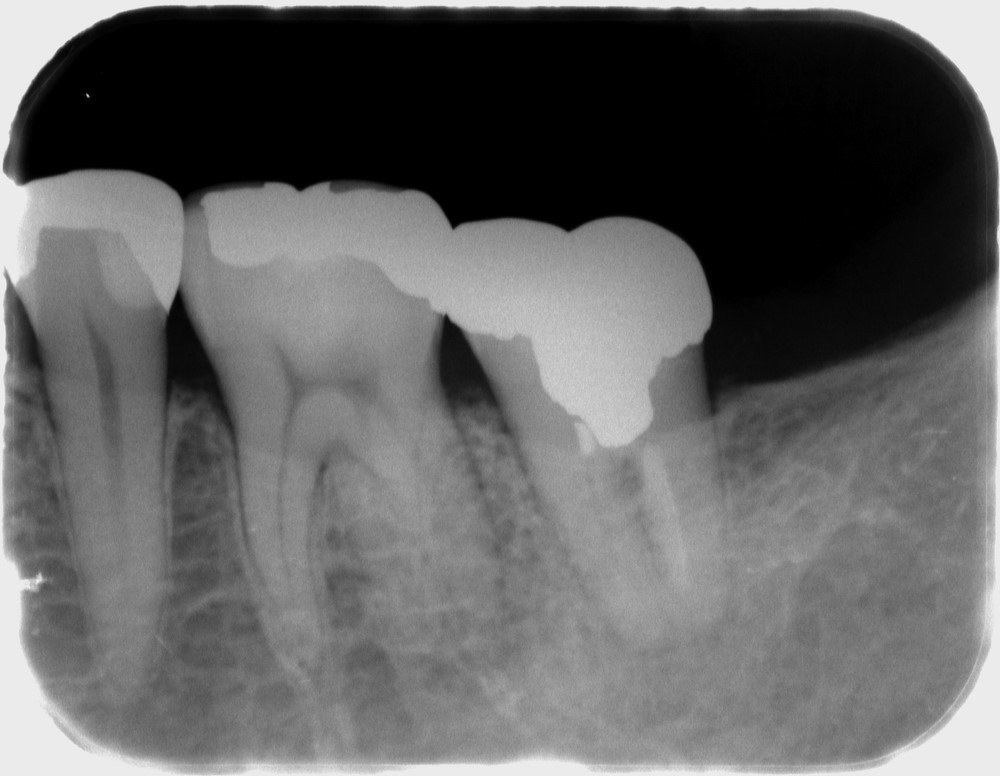

痛みの原因は、このクラウンの装着されている左下7のようです。

レントゲン写真を撮影し、診査したところ、左下7の根尖性歯周炎と診断し、再根管治療を行いました。

術後のレントゲン写真です。写真状のみの判断ではありますが、問題なく治療が完了しています。

術後2年後のレントゲン写真です。痛みも全くなく、写真状でも全く問題ありません。現段階では、この根管治療は成功していると判断できると思います。